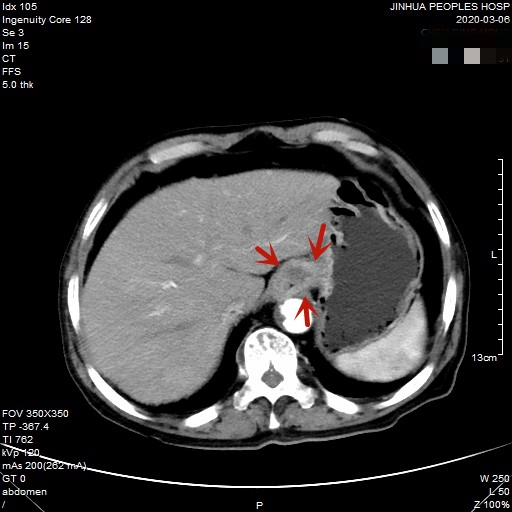

医生予以进一步检查CT增强发现肿瘤倒是没有明显侵犯周围脏器或结构,请我去会诊后,仔细阅片,发现从影像上看还是能够根治性切除的。所以转来胸外科拟进一步行手术治疗。下面是其CT增强的图像:

以上图片红色箭头所指处为贲门部肿瘤